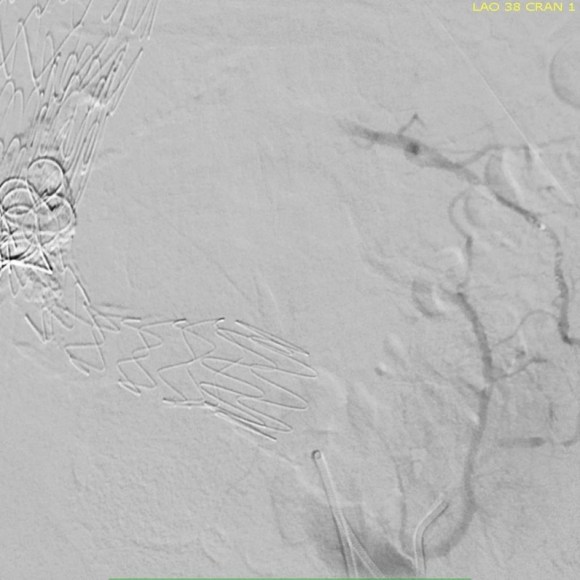

The 3D-VR image view on Aquarius Intuition (TeraRecon) predicts a camera angle of 50 degree LAO to see the branch leaking to the lumbar vessel causing the leak.

Selection of the branch vessel is straightforward as the CTA well illustrates the course of the source iliolumbar vessel. The CTA even showed the loop that was challenging to traverse. The sequence of access involved IIA, branch access with a glide catheter, placing a Rosen wire for anchorage, and pushing the sheath over the glide catheter into the branch vessel, giving stability. Further access into and across the loop was then possible with superselective catheters based on an 0.18 wire system.

Once access into the AAA sac was achieved, coil embolization of the leak cavity chased by glue (NBCA) allowed for obliteration of the endoleak.